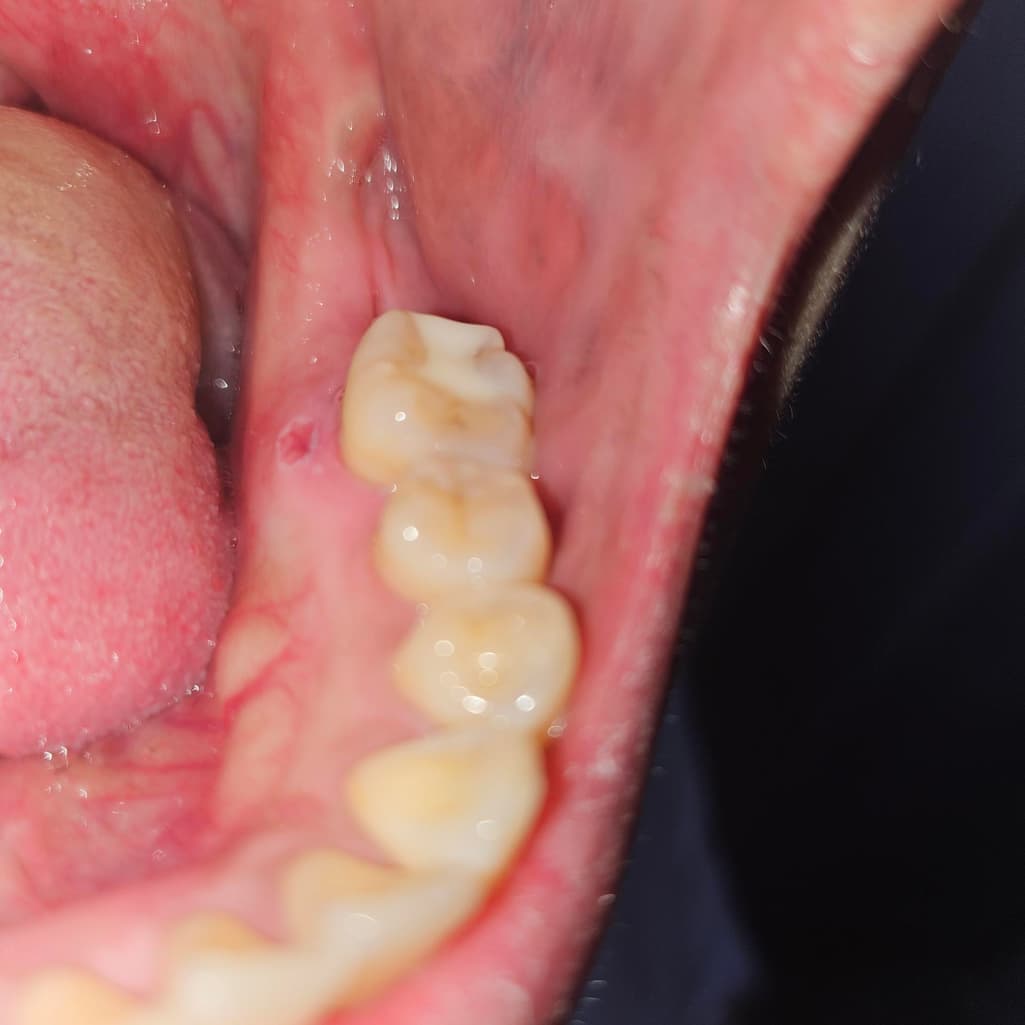

치과치료후 마취주사 통증 헐음 어떻게하나요?

다음주월요일날씌우기로했는데 이거괜찮은건가요

몽우리아직만져져요 턱쪽에 통증도어제보단덜하지만있습니다.

이빨끼리 부딪히면 진동감있어요

마취 주사로 인해 잇몸에 상처가 난 것으로 보이며 보통은 시간이 지나면 저절로 회복됩니다.